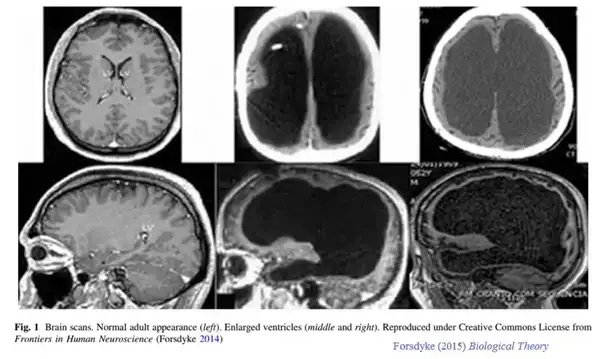

2007 年,《柳叶刀》颁发了一名 44 岁法国男人,因为无诱因左下肢无力,间歇性爆发就诊的病例。大夫查抄他的下肢发现没有异常,思疑是中枢神经系统的问题。于是做了个 CT,成果显示,他有极严重的侧脑室扩张,换句话说,他的脑子只有表层。

这名男纸在出生 6 个月的时辰,因为不明原因的脑积水行脑室分流术,到 14 岁时移除导管及支架。他的大脑在长时候脑积水的侵蚀下,90%已经消逝,IQ 测试只有 75。但他依然正常糊口正常工作,经由过程了本地的公事员测验,在约 30 岁时成婚,已育有一子一女,后代均体健,无神经系统相关疾病等。